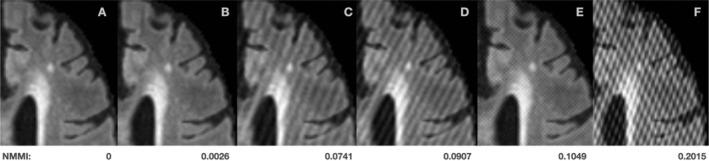

White matter hyperintensities (WMH) of presumed vascular origin are a magnetic resonance imaging (MRI)-based biomarker of cerebral small vessel disease (CSVD). WMH are associated with cognitive decline and increased risk of stroke and dementia, and are commonly observed in aging, vascular cognitive impairment, and neurodegenerative diseases. The reliable and rapid measurement of WMH in large-scale multisite clinical studies with heterogeneous patient populations remains challenging, where the diversity of imaging characteristics across studies adds additional complexity to this task. We present segcsvd, a convolutional neural network-based tool developed to provide reliable and accurate WMH quantification across diverse clinical datasets. segcsvd was developed using a large dataset consisting of over 700 fluid-attenuated inversion recovery MRI scans from seven multisite studies, spanning a wide range of clinical populations, WMH burdens, and imaging protocols. Model training incorporated anatomical information through a novel hierarchical segmentation approach, together with extensive data augmentation techniques to improve performance across varied imaging conditions. Benchmarked against three widely available segmentation tools, segcsvd demonstrated superior accuracy, achieving mean Dice score improvements of 7.8% ± 9.7% over HyperMapp3r, 21.8% ± 8.6% over SAMSEG, and 43.5% ± 7.1% over WMH-SynthSeg across four diverse test datasets. segcsvd also maintained consistently high Dice scores across these test datasets (mean DSC = 0.86 ± 0.08), and exhibited strong, stable correlations with periventricular, deep, and total WMH ground truth volumes (mean r = 0.99 ± 0.01). Additionally, segcsvd was robust to low and moderate levels of simulated MRI spike noise artifacts and maintained strong performance across a range of binary segmentation thresholds and WMH burden levels. These findings suggest that segcsvd may provide more accurate and robust WMH segmentation performance for heterogeneous clinical datasets characterized by varying degrees of CSVD severity.

推测为血管源性的脑白质高信号(WMH)是基于磁共振成像(MRI)的脑小血管疾病(CSVD)生物标志物。WMH与认知功能下降、中风和痴呆风险增加相关,且常见于衰老、血管性认知障碍和神经退行性疾病中。在具有异质性患者群体的大规模多中心临床研究中,可靠且快速地测量WMH仍然具有挑战性,因为各研究中成像特征的多样性给这项任务增加了额外的复杂性。我们展示了segcsvd,这是一种基于卷积神经网络开发的工具,旨在为不同的临床数据集提供可靠且准确的WMH定量分析。segcsvd是使用一个大型数据集开发的,该数据集包含来自7项多中心研究的700多次液体衰减反转恢复MRI扫描,涵盖了广泛的临床人群、WMH负荷和成像协议。模型训练通过一种新颖的分层分割方法纳入解剖学信息,并结合广泛的数据增强技术来提高在各种成像条件下的性能。与三种广泛使用的分割工具进行基准测试时,segcsvd表现出卓越的准确性,在四个不同的测试数据集上,其平均骰子系数得分比HyperMapp3r提高了7.8%±9.7%,比SAMSEG提高了21.8%±8.6%,比WMH-SynthSeg提高了43.5%±7.1%。segcsvd在这些测试数据集中也始终保持较高的骰子系数得分(平均DSC = 0.86±0.08),并且与脑室周围、深部和总的WMH真实体积表现出强而稳定的相关性(平均r = 0.99±0.01)。此外,segcsvd对低水平和中等水平的模拟MRI尖峰噪声伪影具有鲁棒性,并且在一系列二元分割阈值和WMH负荷水平上都保持了强大的性能。这些发现表明,对于以不同程度的CSVD严重程度为特征的异质性临床数据集,segcsvd可能提供更准确、更稳健的WMH分割性能。